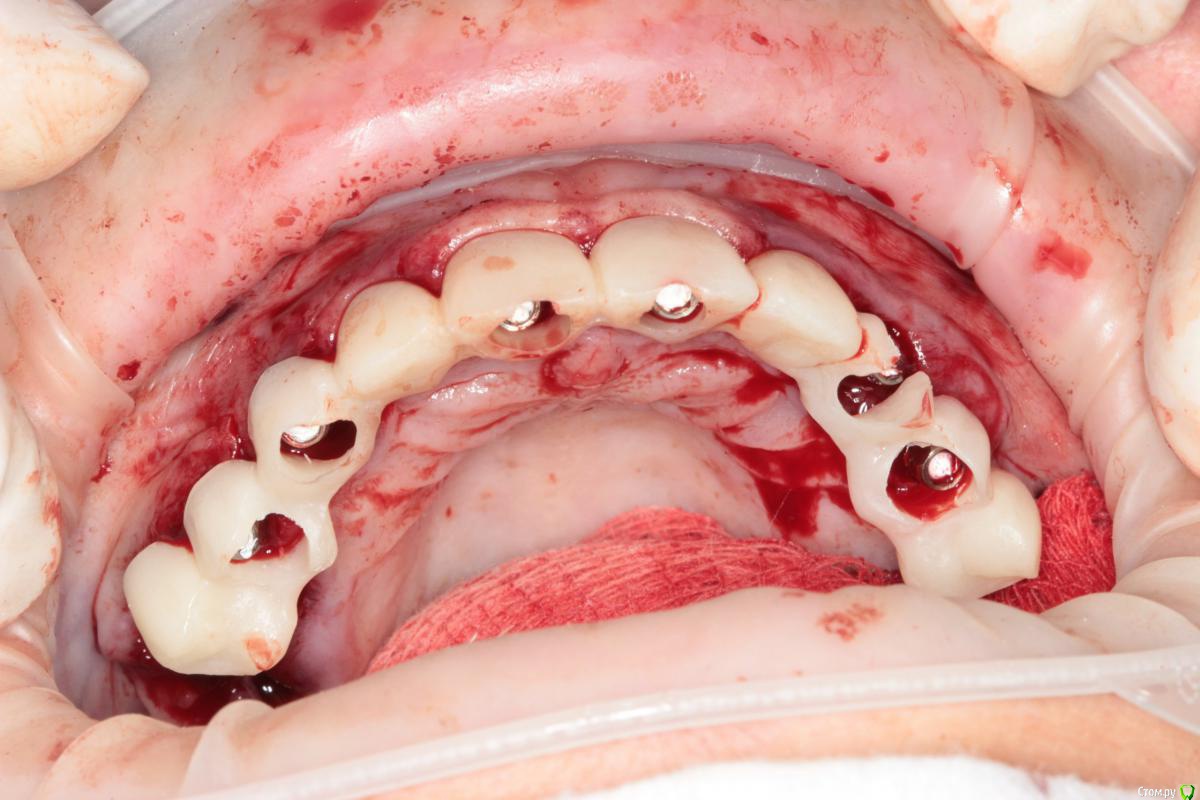

Популярный пост Abuk Опубликовано 24 ноября, 2015 Популярный пост Поделиться Опубликовано 24 ноября, 2015 Планировали 8 имплантатов.Буду рад конструктивной критике.Фото с мокап.Через 6 днейДалее хотели поставить 6 ки, она отказалась (не хотели синусы)и решили все по-другому .Через 2мес пришла с отколотыми консолями )Прошу прощения ,что ортопедию выложил не в том разделе), не хотел делить. 26 1 Ссылка на комментарий

Abuk Опубликовано 24 ноября, 2015 Автор Поделиться Опубликовано 24 ноября, 2015 (изменено) Радикально Вы. Что оставили ей после имплантации-это инд аббатменты? На них мокап одели и нагрузили сразу? У всех был торк хороший? Или это временные абб? Что за систему использовали? В планах консоль назад, правильно я понимаю?Спасибо.увидев такую работу,сам так же подумал бы). Но там подвижность 2-3 ст. ближе к 3. Мосты болтались ,2 ки в хлам. 1 ки только стабильны. Снимал мосты,проводил кюретаж. Решил дернуть.Абатманы временные, тех. сделал на них коронки. Система анкилоз. Работа,на посл. фото, постоянная . Имплы в области 4 и по одному моляру ,консоли. Мок ап был до имплантации . По нему шаблон. Стабильность 15 -20 на 23 , остальное больше 30. Изменено 24 ноября, 2015 пользователем Abuk 1 Ссылка на комментарий